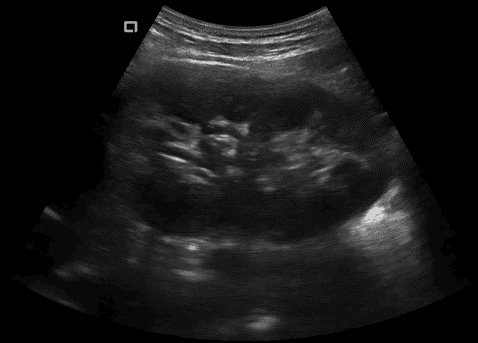

Konvexsonde (C5-2Ks) 3,3 MHz 2 - 5 MHz R50 Abdomen, Gynäkologie, Geburtshilfe, Urologie